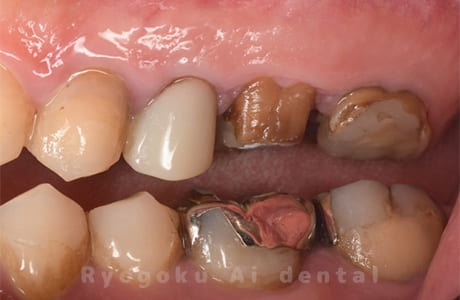

Case12

-

- 原因

- 縁下カリエス

- 治療内容

- クラウンレングスニング、ジルコニアクラウン修復

- 治療費用

- 約220,000円

被せ物の中から臭いがするとのことで、被せ物を外したところ大きな虫歯となっていました。このまま被せてしまうと被せ物が外れやすいため、埋まっている歯を出すためのクラウンレングスニング処置を行い、その後、ジルコニアクラウンで被せ物を行いました。